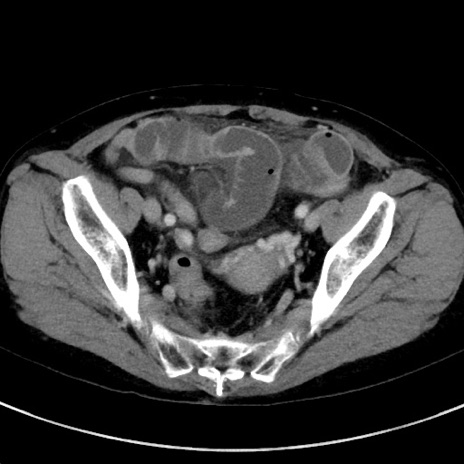

症例23(横断像)

【症例】70歳代女性

【主訴】下腹部痛・嘔吐

【現病歴】2日前より腹痛あり。昨日嘔吐あり。症状改善しないため来院。

【既往歴】胃GISTに対して胃部分切除後。

【身体所見】BT 37.1℃、BP 128/77mmHg、腹部:平坦・軟、下腹部に圧痛あり。

【データ】WBC 10200、CRP 0.31